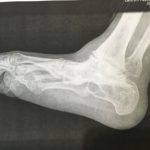

przed operacją

RTG przed operacją